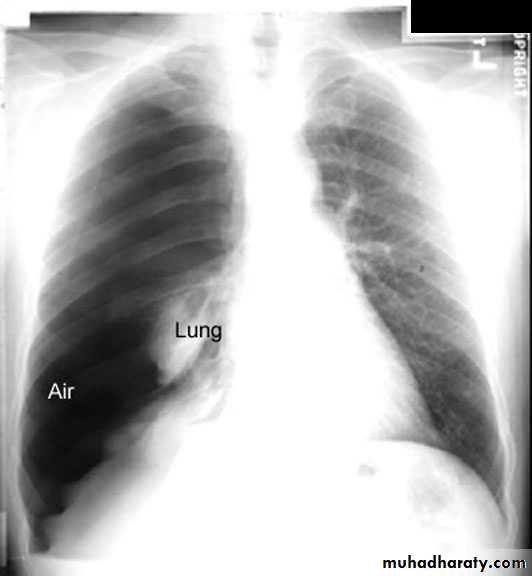

Pleural diseasespleural effusionpneumothorax hydro pneumothoraxpleural calcifications & thickeningpleural tumour

Pleural effusion ( free)